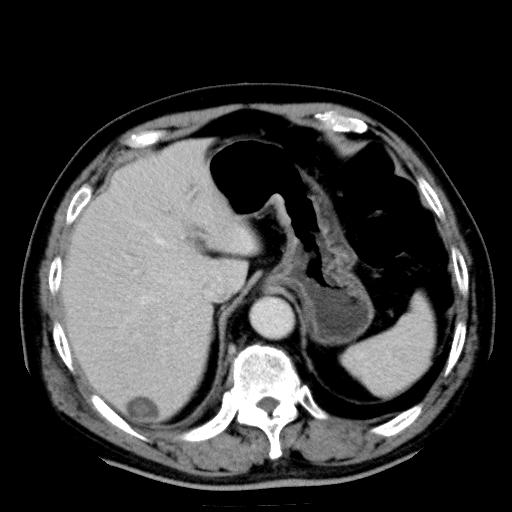

以下是引用zhctwbh在2008-8-23 14:20:00的发言:[br]囊肿合并出血

以下是引用zjb在2008-8-23 16:41:00的发言:[br]囊肿并出血可能性大。